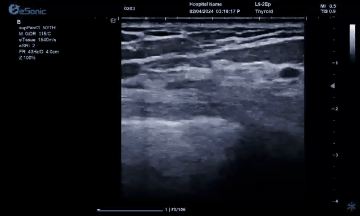

银河官网医疗(ESI)设计的原数精准准台式平台,采用软声束成像系统,采集帧频达到10000Hz/S,每秒处理数据达10亿次,这是超声历史上首次做到准台式机型使用超快速平台。使用此平台,加快了临床图像的帧频采集速度和屏幕显示的刷新速度,获得更加清晰的图像,对女性两腺较细小病灶有较高的细微结构分辨率,有助于增强诊断和治疗决策的信心。